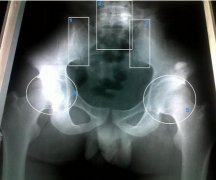

强直性脊柱炎检查

• 强直性脊柱炎检查常用三种方法